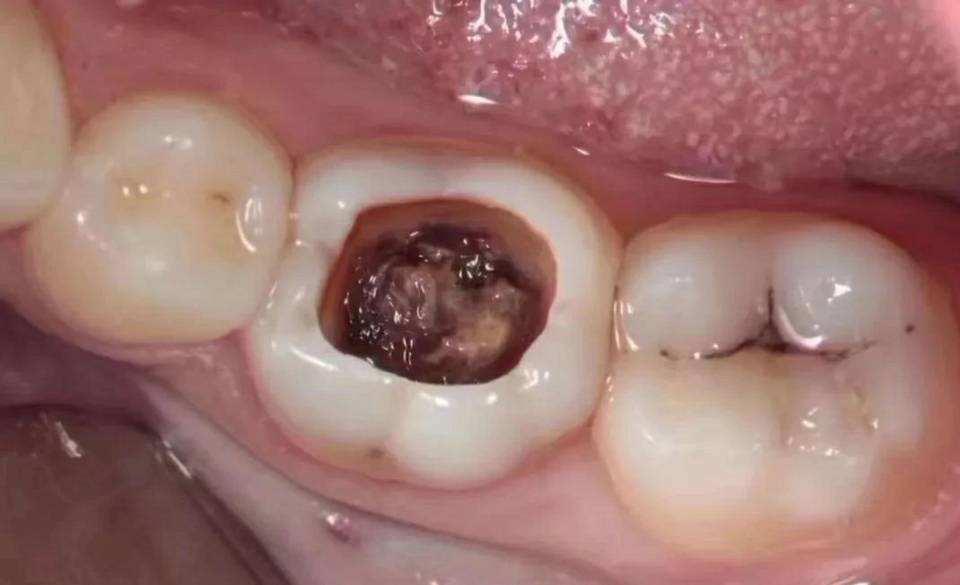

牙齿有一个比较大的黑洞,晚上牙齿比较疼...不知道有多少人也是这种情况?如果你有这个情况,可能你要做根管治疗了!

一般情况下,牙齿龋坏严重、严重的牙齿隐裂引起牙髓坏死,出现炎症以及根尖炎症并且无法进行保髓治疗的情况需要进行根管治疗。